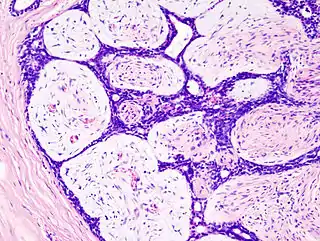

Fibroadenoma

El tumor benigno más común de la mama femenina es el fibroadenoma. Como su nombre indica, es una neoplasia formada por el tejido fibroso y glandular. Ocurre en cualquier etapa del período reproductivo de la vida y es algo más frecuente antes de los 30 años de edad. Se dice que el tumor aparece como resultado del aumento de sensibilidad de un foco mamario a los estrógenos.

![]() Imagen histopatológica de fibroadenoma de mama. Tinción hematoxilina-eosina. | ||

Crece por lo regular como un nódulo pequeño y centrífugo que suele ser netamente circunscrito y libremente móvil sobre el parénquima mamario adyacente.[1] Aunque un fibroadenoma, así como los papilomas intraductales, son crecimientos anormales, no son cancerosos y no se pueden propagar del seno hacia otros órganos.[2]